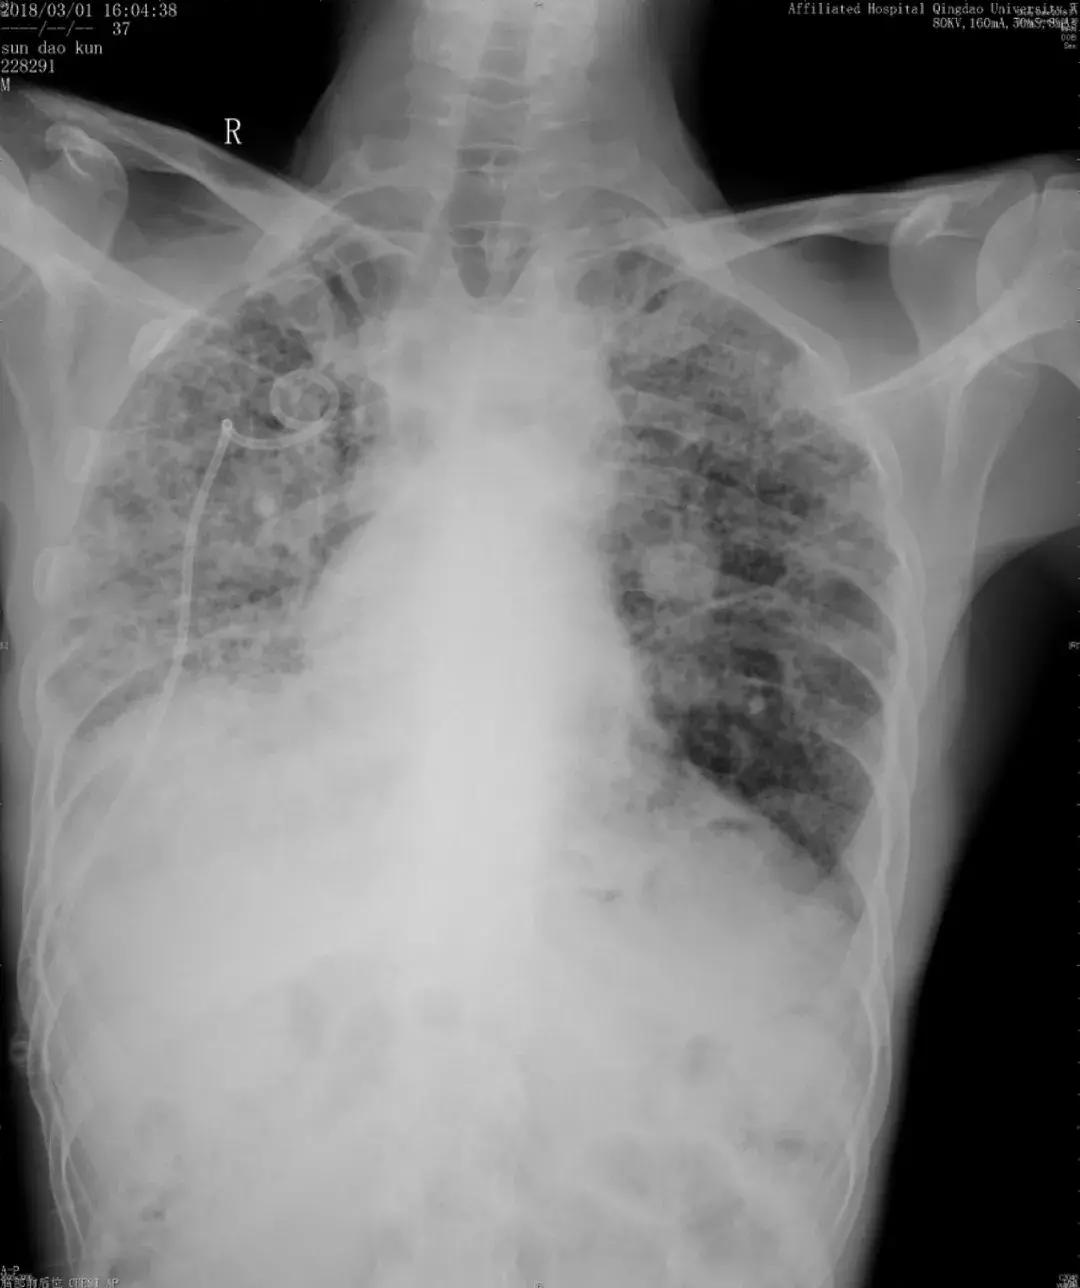

随访:活动性呼吸困难逐渐加重,出现了气胸

由于儿子反复治疗的花销已经很大了,这位患者诊断后没有特别治疗,曾去过多家医院,考虑过肺移植,但由于是遗传性疾病只好作罢。随后在我院随访,呼吸困难逐渐加重,间质改变越来越严重,原来是上肺比较明显,后来下肺病变也加重了,再后来右上肺出现大泡,最后出现气胸,反复住院,这个患者后来再也没有来了……

胸部正位片(2018-03-01):